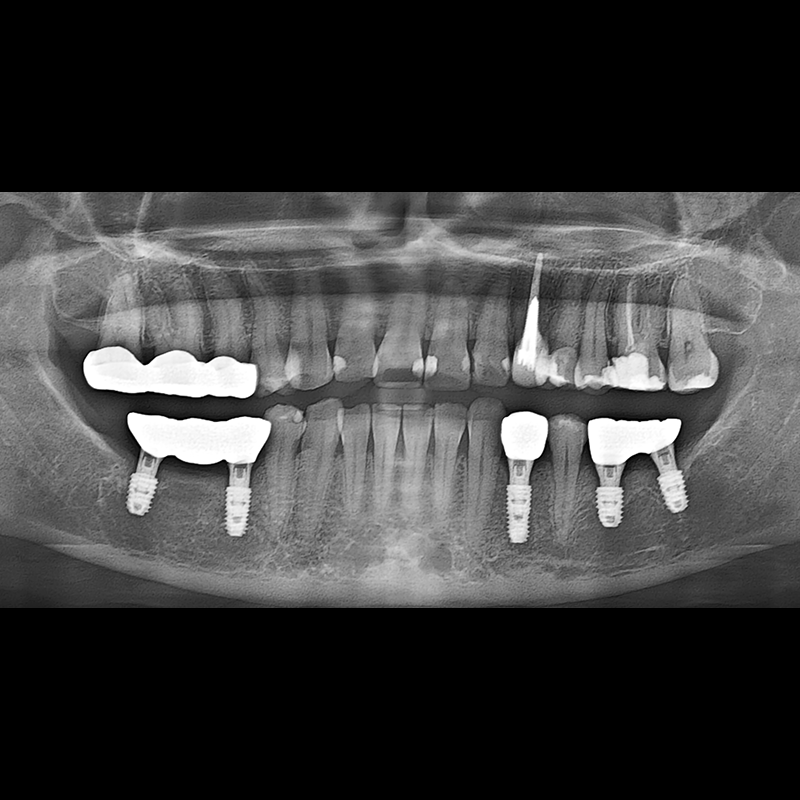

BEFORE AFTER

インプラント手術事例 2025.05.30

欠損した歯の部分と、生かしにくい歯の位置にインプラントを植立しました。